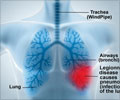

Unclean dentures provide a new surface where disease-causing microbes can colonize. People who wear dentures may then be aspirating (inhaling) saliva containing harmful microbes into their lungs, where an infection can then take hold, said the researchers from Cardiff University, UK. In the study, they took mouth, tongue, and denture swabs from a group of patients in the hospital who had pneumonia and wore dentures. They then compared this to samples taken from denture-wearing patients in care homes who did not have pneumonia.They then analyzed the samples to identify the abundance and types of microbes present in the samples (1✔ ✔Trusted Source

Association Between Dentures and Pneumonia-Causing Bacteria

"We were expecting to see a difference but were surprised to see 20 times the number of potentially pneumonia-causing bacteria on dentures in people with pneumonia, compared to people without," said lead author Dr. Josh Twigg, from the university.While the study, published in the Journal of Medical Microbiology, identifies a possible connection, Dr. Twigg stresses: "You certainly couldn't say that people got pneumonia because they were wearing dentures. It's just showing that there is an association there. This research is an early step in trying to unravel that puzzle of what exactly is the sequence of events."